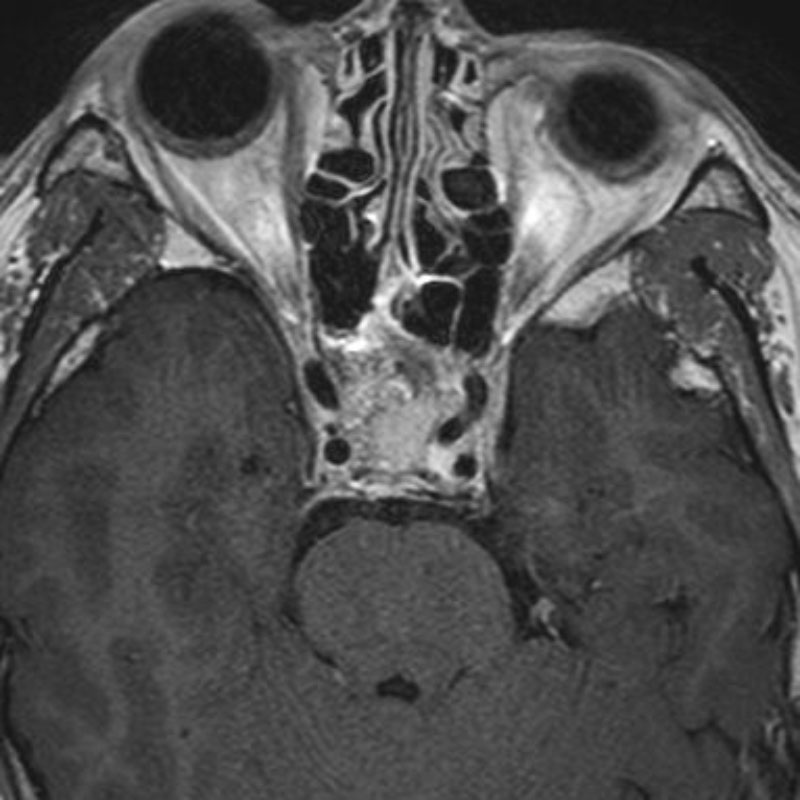

右傍矢状洞髄膜腫

頭蓋内腫瘍摘出術

No.’23_63 手術前1

No.’23_63 手術前2